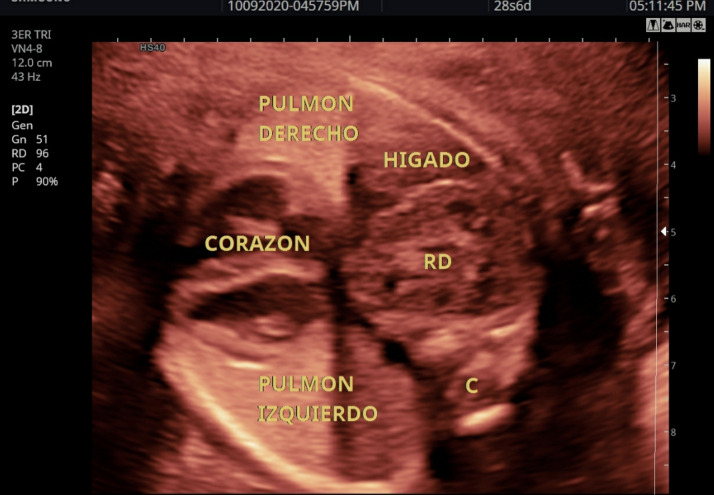

Material and methods: We report the case of a 28-week fetus in which, on ultrasound imaging, a mass was observed displacing the heart and lung in the right hemithorax, which was was confirmed by magnetic resonance (MR) to be an ectopic intrathoracic kidney (ITEK). After birth, the neonate was approached by laparoscopy to place a mesh in continuity with the diaphragm, leaving the kidney in the abdomen, with good evolution. A search was conducted in the PubMed, Embase and Cochrane databases for cohorts, case reports and case series of prenatal diagnosis of intrathoracic kidney in the fetus. Information was retrieved regarding design, population, imaging diagnosis, treatment and prognosis.

Results: The search identified 8 studies that met the inclusion criteria, reporting a total of 8 cases. Ultrasound diagnosis showed ectopic intrathoracic kidney associated with diaphragmatic hernia in all the subjects. Fetal magnetic resonance imaging (MRI) was also used in 5 cases.